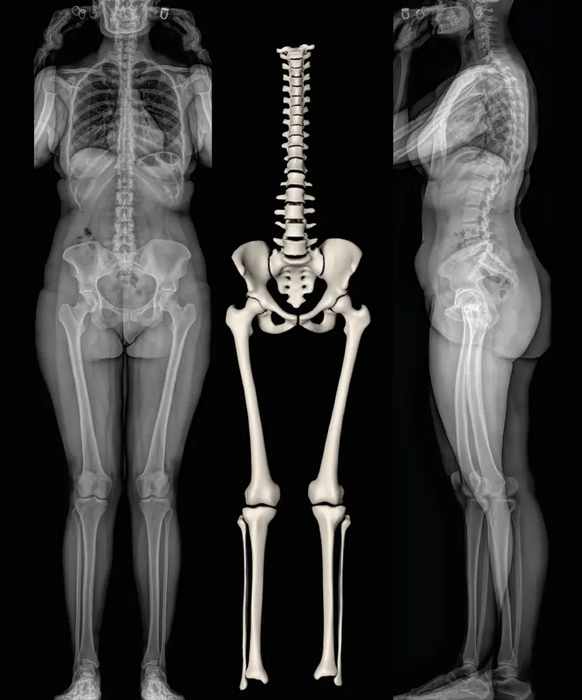

EOS xray imaging

Technique

- low dose biplanar digital xrays

- two orthogonal xrays obtained simultaneously

- recreate 3D image

Advantage

- lower radiation than both CT and xray

- includes spinopelvic anatomy

Disadvantage

- not offered in all centers